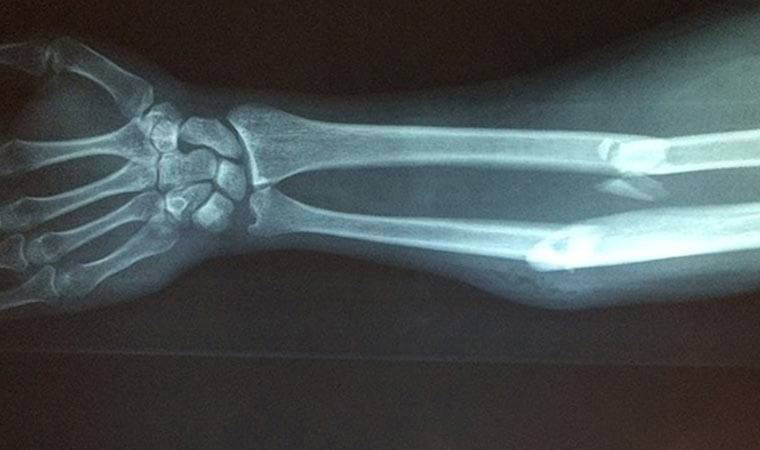

Kaya'nın SİÜ Teknik Bilimler Meslek Yüksekokulunda Öğretim Görevlisi Cüneyt Özdemir ve Kütahya Sağlık Bilimleri Üniversitesi Evliya Çelebi Eğitim ve Araştırma Hastanesi Radyoloji Uzm. Dr. Mehmet Ali Gedik ile derin öğrenme teknolojisi kullanarak geliştirdiği sistem ile ilgili hazırlanan makale uluslararası kabul gören dergilerden "Traitement du Signal"de yayınlandı.Akademisyenler yapay zekanın en önemli konularından olan derin öğrenme metotları ile çalışan sistemle ilgili bir de web sitesi oluşturdu. Herhangi bir gerekçe ile kişinin kemik yaşı tespiti gerektiğinde el bilek görüntüsü sisteme yüklenerek, bir dakikanın altında sürede tespit yapılabilecek.

Doç. Dr. Yılmaz Kaya, sağlıkta yapay zeka ile "makine öğrenme", "medikal sinyal ve görüntü işleme", "doğal dil işleme" gibi çeşitli çalışmalar yaptıklarını söyledi.Bu kapsamda akademisyenler Özdemir ve Gedik ile yaptıkları çalışmada kemik yaşı tahmini için radyologların iş akışını hızlandıracak bir çalışma yürüttüklerini ifade eden Kaya, sol el bilek grafisinden derin öğrenme teknolojisi kullanılarak bilgisayar temelli bir karar destek sistemi geliştirdiklerini belirtti. Verileri Kütahya'daki 4 hastaneden elde ettiklerini dile getiren Kaya, "Yapay zeka tekniklerini kullanarak el grafilerinden kişinin yaşını tespit etmeye çalıştık. Yaş tespiti çok zahmetli bir şekilde radyologlar tarafından belirleniyor ama bilgisayar sistemiyle çok daha kolay ve hızlı şekilde gerçekleştirebilirsiniz." dedi. Kaya, el grafisinden kemik yaşı tespitinin daha önce yaklaşık 2 saat sürdüğüne işaret ederek, geliştirdikleri sistemle yaş tespit süresinin saniyelere düştüğünü kaydetti.

Öğretim görevlisi Cüneyt Özdemir de derin öğrenme yöntemiyle sol el bilek grafisinden kemik yaşı tespitine yönelik çalışmaların 18 yaş altı ve 18 yaş üstü bireylere yönelik iki aşamadan oluştuğunu belirtti.

Özdemir, "Ülkemizde bu işlem için radyologlar genellikle gök atlası dediğimiz sistemden yararlanmakta. Bu yöntemde radyologlar bakış açılarına göre farklı sonuçlar da elde edebiliyorlar. Bu çalışmayla bu işlemi otomatikleştiren, radyologlar için bir karar destek sistemi geliştirdik. Bu sistem uzmanların iş akış sürecini hızlandırıp, kolaylaştıracak." diye konuştu.

18 yaş üstü bireylerin kemik yaşının tespitine yönelik de çalışma yaptıklarını aktaran Özdemir, "18 yaş üstü ile ilgili çalışmalar maalesef ülkemizde ve dünyada az. 18 yaş üstü kemik yaşı tespiti için yüz ve dişlerle ilgili yapılan çalışmalar var. Biz ilk defa el bilek grafisinden 18 yaş üstü kemik yaşının tespitine dönük de bir çalışma yaptık. Bu yöntemle başarılı bir sonuç elde ettik. Bu, literatürde derin öğrenme yöntemiyle 18 yaş üstü kişilerin kemik yaşı tespitine dönük yapılan ilk çalışmalardan biri olma özelliğini taşıyor." ifadelerini kullandı. Özdemir bu konuda da makale hazırladıklarını anlatarak, çalışmanın yayınlanmasını beklediklerini belirtti.